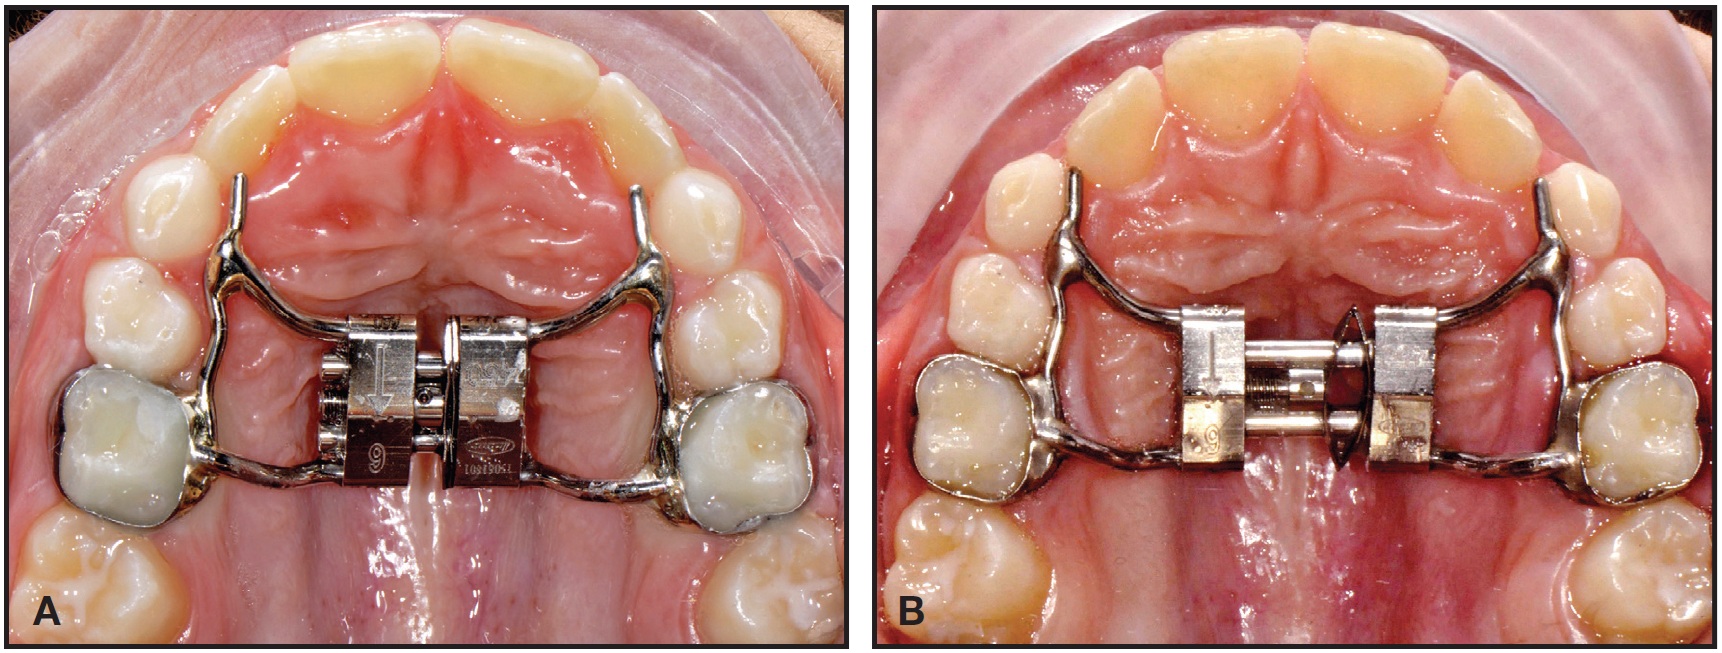

The leaves are preactivated in the laboratory to deliver 3mm of expansion. The screw is blocked with metal ligatures or a special clip, which is removed after cementation (Fig. 2).

Fig. 2 A. Preactivated expander fitted in mouth, with metal ligatures blocking expansion screw. B. Ligatures removed after bonding.

A Leaf Expander was bonded to bands on the second deciduous molars, with extensions to the canines and first deciduous molars (Fig. 5A).

The screw was activated following the described protocol to produce 6mm of expansion (Fig. 5B).